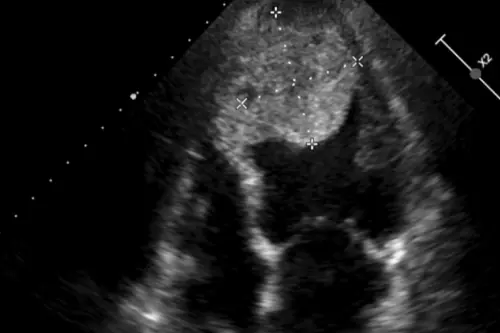

▲超音波檢查發現心臟有5公分大血栓。(圖/台北慈院提供) 隨後在第2次手術中,醫療團隊為病人換上長效型輔助器,不料右心室功能惡化,再緊急加裝右心室輔助器,並延後關閉胸腔以處理出血風險;到第3次手術時,則移除右心室輔助器並閉胸,患者這才逐步穩定,並等到合適的心臟捐贈者,完成心臟移植後已康復返家。